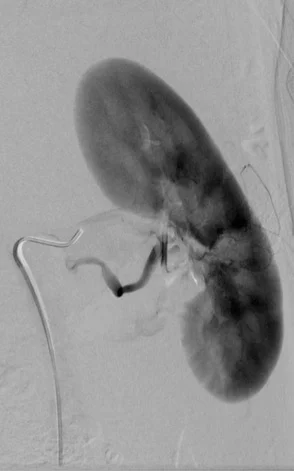

TF Trauma Case 7

48 year old s/p MVA with hypotension and left sided flank pain.